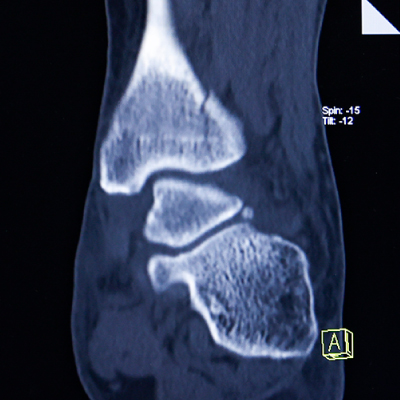

Ⅹ線CT装置(16列マルチスライス) Siemens SOMATOM Scope

X線投影データをもとに、コンピューターによって再構成された画像により体内の形態情報を得ることができます。

細かいスライスデータにより、目的部位の三次元画像や任意の断面の画像を作成し、正確な診断に寄与する画像データを得ることができます。

使用するX線量は最適化され、被ばくの低減に努めています。

予約不要。即日検査いたします。(単純CTのみ)

医師の診断~CT撮影まで、受診日当日に即日検査いたします。

ご希望の方は栗東診療所を受診のうえ、医師にご相談ください。